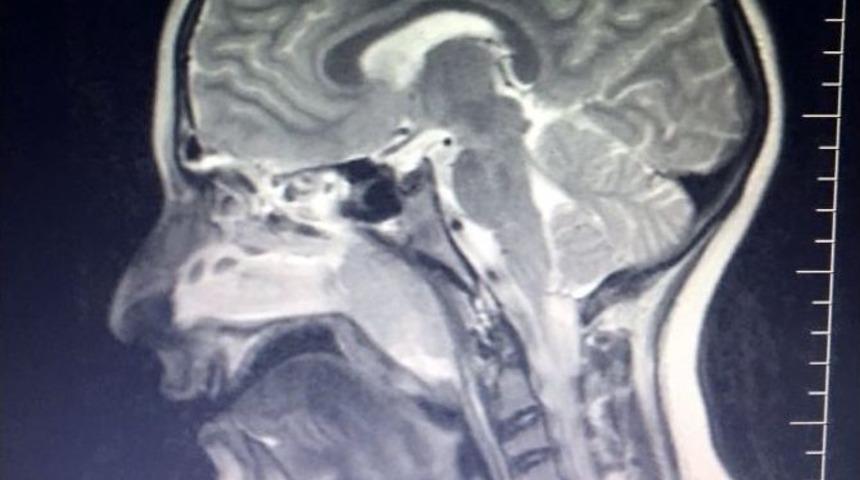

Geniz eti büyümesi çocuklarda uyku ve solunum zorluğu gibi birçok soruna yol açıyor.Geniz eti, zamanında tedavi edilmediği takdirde ciddi sorunlara yol açabiliyor. Gecikmeden tedavisinin yapılması çocuğun sağlıklı gelişimi açısından son derece önemli.Bebekliğinden beri solunum sıkıntısı yaşayan ve yıllardır astım ile bronşit tedavisi gören Yiğit Ahmet Osoydon, geniz eti ameliyatıyla dertlerinden kurtuldu.Yiğit Ahmet Osoydon’un, geniz eti teşhisi koyulmadan önce üzerinden yıllar geçen bir hikayesi var. Medicana Bahçelievler Hastanesi’nde Kulak Burun Boğaz Uzmanı Op. Dr. Volkan Kahya tarafından Yiğit Ahmet’in operasyonu gerçekleştirildi.9 yaşında olan Yiğit Ahmet bebekliğinden beri solunum sıkıntısı yaşamış ve gittiği her yerde astım ve bronşit tedavileri uygulanmış.Yiğit Ahmet’in annesi, ilk doğduğunda doktorun geniz eti veya saman nezlesi olabileceğini söylediğini ancak küçük bir çocukta böyle bir şey olabileceğini tahmin etmediklerini belirterek, "Çocuğumu ayda 2-3 kez doktora gitmek zorunda kalıyordum. Polip olduğu hatta kulağında delik olduğu söylendi. Allerji testleri yapıldı, 6 ay süren ilaç tedavisi gördü fakat sıkıntılar hala devam ediyordu. Son 1-2 aydır horlama ve rahatsızlıklar iyice artmaya başladı ve ilaç tedavisi sürecinde eğitim hayatına ara vermek zorunda kalıyorduk. Bu süreç böyle devam etti ve son çareyi pediatri doktorunun kulak burun boğaz hekimine yönlendirmesi ile Medicana Bahçelievler Hastanesi’ne geldim. Hastanın yapılan ayrıntılı endoskopik muayenesinde burun içini ve genzini dolduran kitle görüldü, kötü huylu bir tümör olmasından şüphelenilerek boyun MR çekildi. Çekilen boyun Mr nda dev bir geniz eti olduğu tespit edilerek acil olarak ameliyat alında. İkili ulaşım yöntemi uygulandı hem geniz bölgesinden hem de burun içerisinden endoskopik kamera ile geniz eti temizlendi. Bu süreç 3 günün sonrasında başarılı bir şekilde sona erdi. 4. gün gülen yüzlerle açtık gözlerimizi. Gitmediğim doktor ve hastane kalmamışken ve hatta umudumu yitirmeye başladığım şu günlerde yaşadığım en güzel olaylardan biri oldu oğlumun eski sağlığına kavuşmuş olması.Horlamasını kilosundan diye düşünüp kötüyü düşünmekten hep kaçtık. Bugüne kadar uykusuz ve huzursuz geceler geçirdik, artık buna fırsat vermek istemiyoruz. Bu yaşına kadar devam eden bu durum oğlumun uykusuz ve huzursuz geçen geceler yaşamasına sebep oldu ve spor faaliyetlerinde arkadaşlarına göre daha çok efor sarf etmek zorunda kaldı. Bundan sonraki sağlıklı hayat süreçte her şey çok daha güzel olacak" dedi.